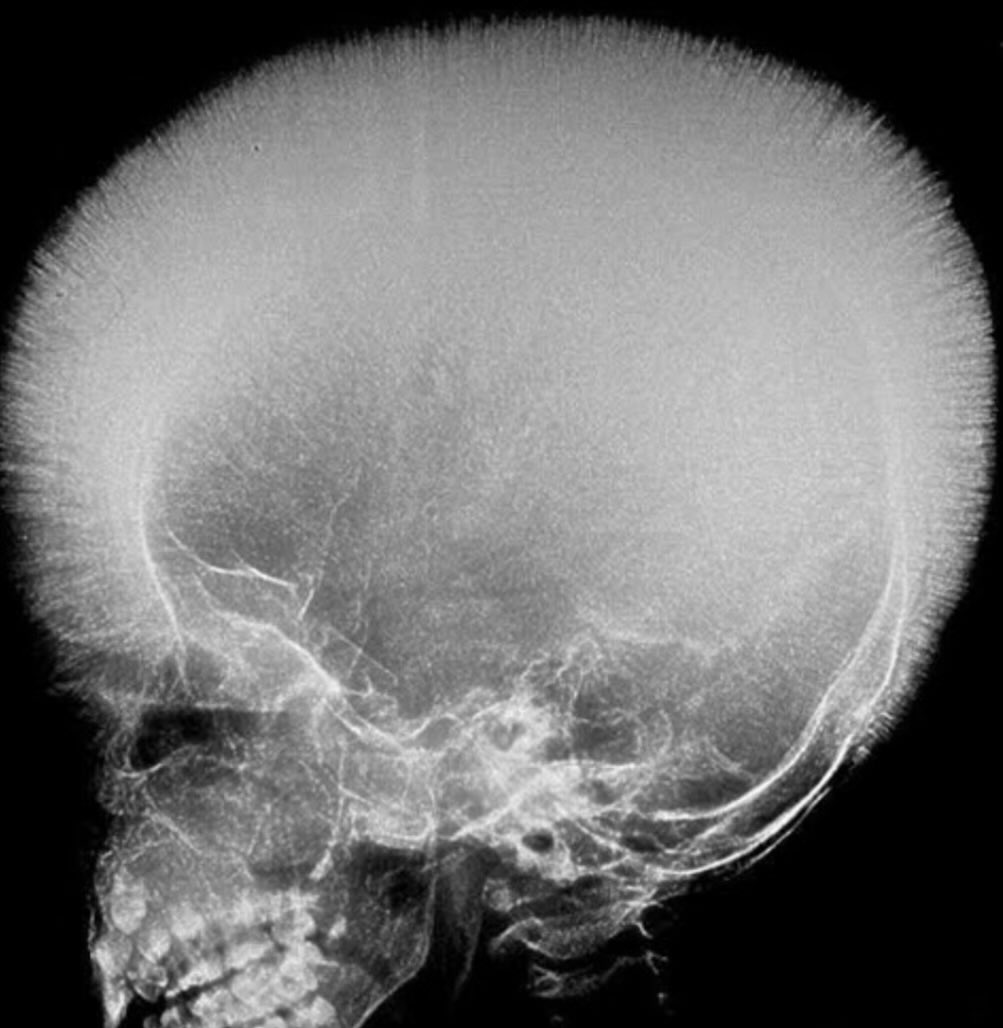

@DrNikhilMD

Dr. Nikhil Agrawal

2 months

Which conditions can cause this?